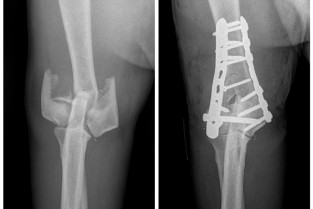

Rejoignez-nous à Bédoin du 5 au 8 juin pour une formation exceptionnelle en orthopédie et traumatologie, orchestrée par le GECOV. Plongez au cœur des affections du coude et de l'épaule chez les chiens et les chats. Le programme, méticuleusement conçu, vous offre une opportunité inégalée d'apprendre des 10 formateurs, chacun expert dans leur spécialité. Cette formation est votre passerelle vers l'excellence en orthopédie et traumatologie. Venez enrichir vos connaissances, affiner vos compétences et élargir votre réseau professionnel dans un cadre idyllique. Ne manquez pas cette occasion unique de faire progresser votre pratique et de garantir le meilleur soin à vos patients.

- réaliser précisément l’examen orthopédique du coude et de l’épaule ;

- décrire les principales affections orthopédiques du coude et de l’épaule ;

- d’interpréter les examens d’imagerie du coude et de l’épaule ;

- de proposer un traitement médical ou chirurgical adapté à l’affection diagnostiquée ;

- d’établir le pronostic fonctionnel du coude et de l’épaule après traitement.